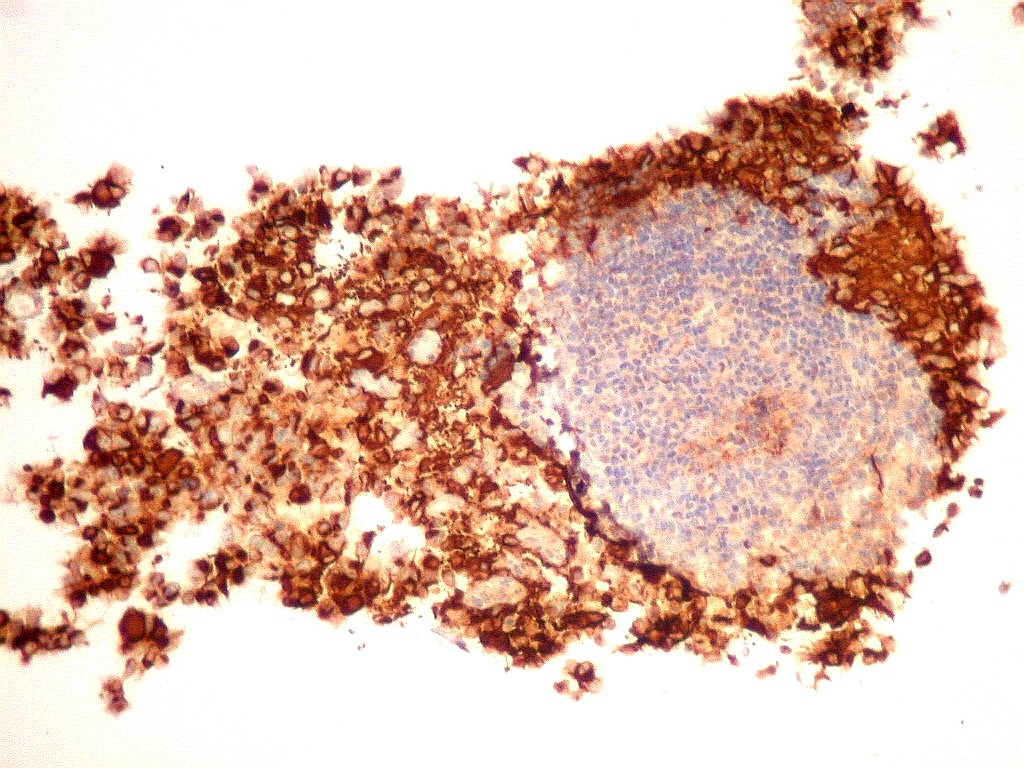

GFAP.     O filamento intermediário do citoesqueleto que caracteriza os astrócitos é forte e difusamente positivo nas células neoplásicas deste tumor teratóide-rabdóide atípico.  Indica diferenciação astrocitária no tumor.  O folículo linfóide e vasos proliferados são negativos.  O epêndima  do III ventrículo, onde o tumor está localizado, também é GFAP positivo.